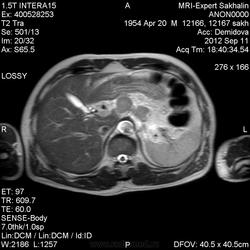

Мужчина по направлению врача с жалобами на боль в животе., снижение массы тела за короткий промежуток времени.Рентгеноскопия желудка не проводилась.На ФГДС-язва кардиального отдела.Онконастороженность.Больше никаких данных.При биопсии опухолевые клетки не обнаружены.У меня сложилось несколько другое мнение.Или ошибаюсь?

Инфильтративная форма рака желудка, преимущественно по малой кривизне в верхней трети тела, субкардии, с инфильтрацией малого сальника.

Спасибо, Люба!Ты подтвердила мои самые худшие предположения.Лимфаденопатия тоже есть, не ошибаюсь?

Для меня непривычно толстые срезы). Могу ошибаться, но вероятно, что это мтс в парааортальные л/у . Биопсия при ФЭГДС? Тогда всё правильно, если считать рак подслизистым.

Мне вообще непривычно диагностировать рак желудка по МРТ.Именно эти ЛУ я  указала.

Утром звонила гистолог-подруга. Сообщила , что у пациента аденокарцинома.Первое гистологическое исследование проводил другой врач.Очень грустно.